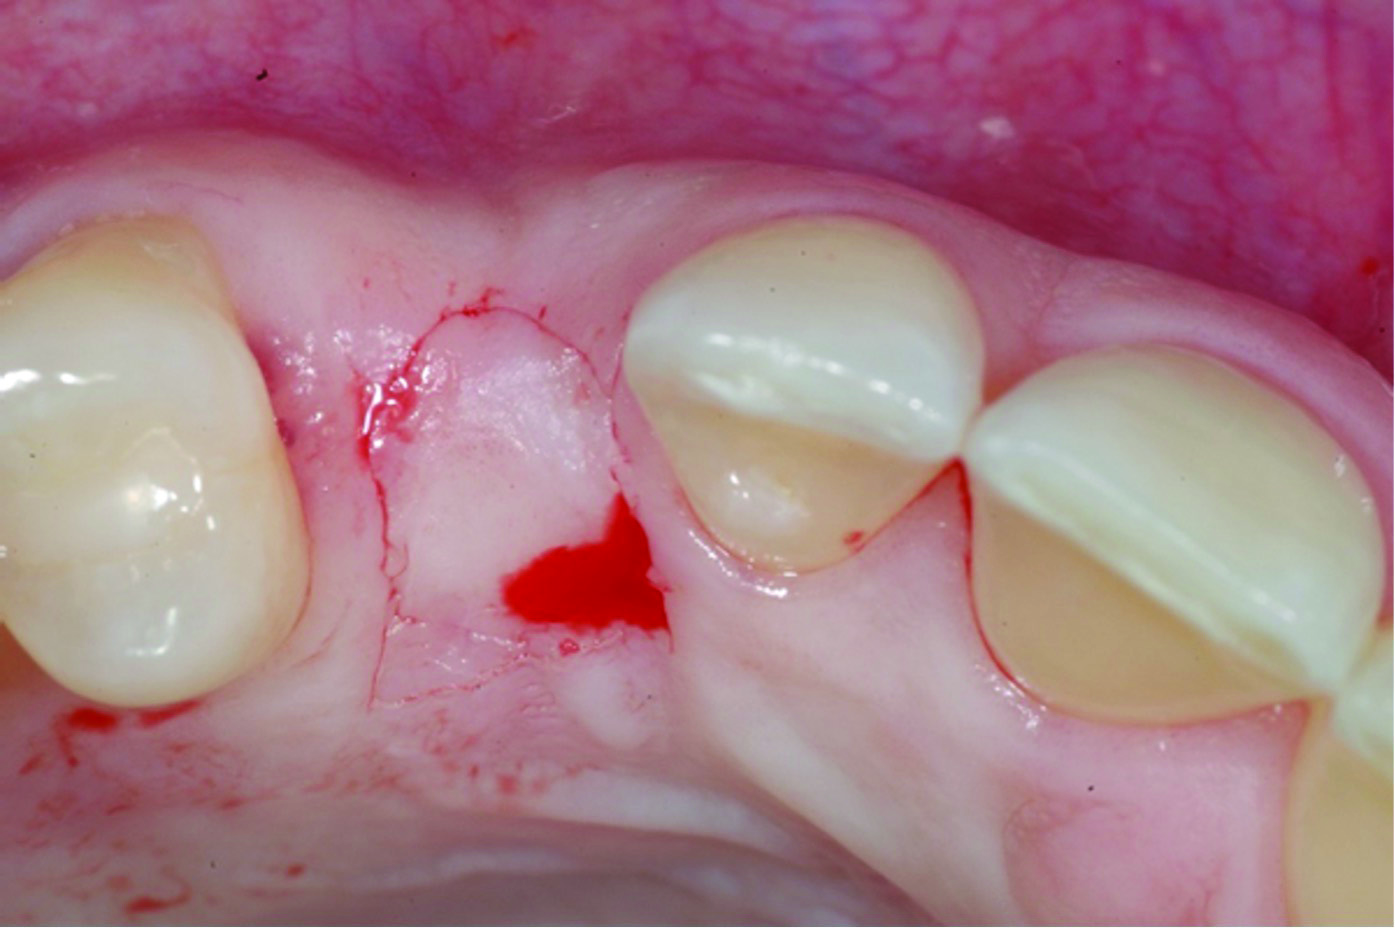

Fig 9: initial presentation;

Figure 9

Fig 10: healing abutment placement with FGG; Fig 11: 2 months post-treatment.

Figure 10

Fig 11: 2 months post-treatment.

Figure 11

When a lack of KMW is noted, suggested treatments may include the use of an apically positioned flap (APF)20 (Figure 6 through Figure 8) or a combination of APF with an FGG (Figure 9 through Figure 11) or tissue alternatives.21 Because of the nature of the recipient site preparation for an FGG or tissue alternative, such as ADM, AXDM, or CM, there is a risk of wound dehiscence and a potential negative effect on the healing of the bone augmentation or on osseointegration if the grafting is done at the time of ridge augmentation or implant placement. Therefore, the preferred treatment time for increasing KMW with an FGG, ADM, AXDM, or CM is either prior to implant placement or after healing of the implant at the healing abutment connection (Table 1). MT can be increased using the roll technique (Figure 12 through Figure 14)22,23 or by adding a CTG (Figure 15 and Figure 16), ADM, AXDM, or CM (Figure 17 and Figure 18), either at the time of implant placement or healing abutment connection (Table 1).24,25